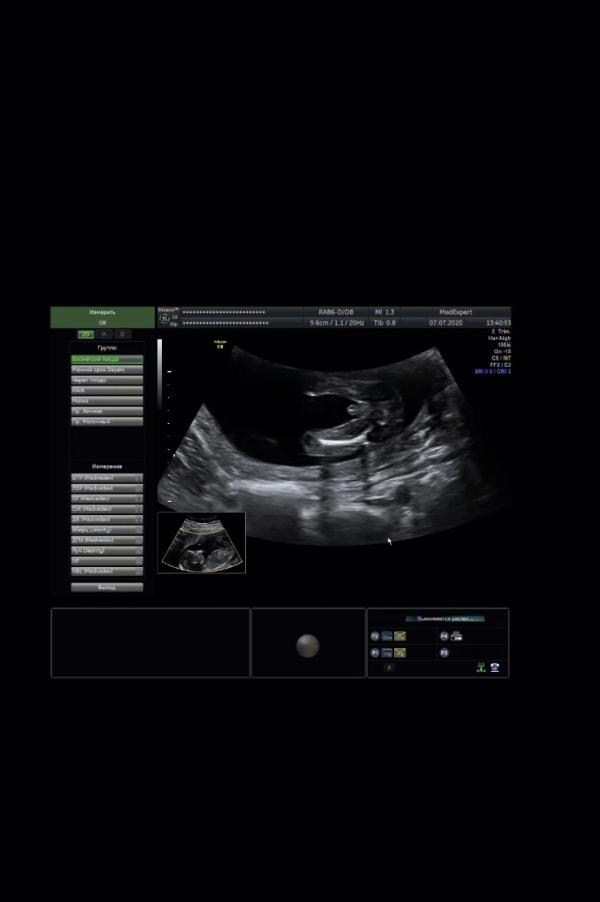

Сегодня очень волнующий день, сынок показал себя 🥰

Это было настолько крупным планом, что ошибки быть просто не может😁

Очень активничал на узи, махал руками, ногами😍

Увидели даже маленькие пяточки 😁

Я стану мамой МАЛЬЧИКА!!!🥰😁🤰🏽🥳